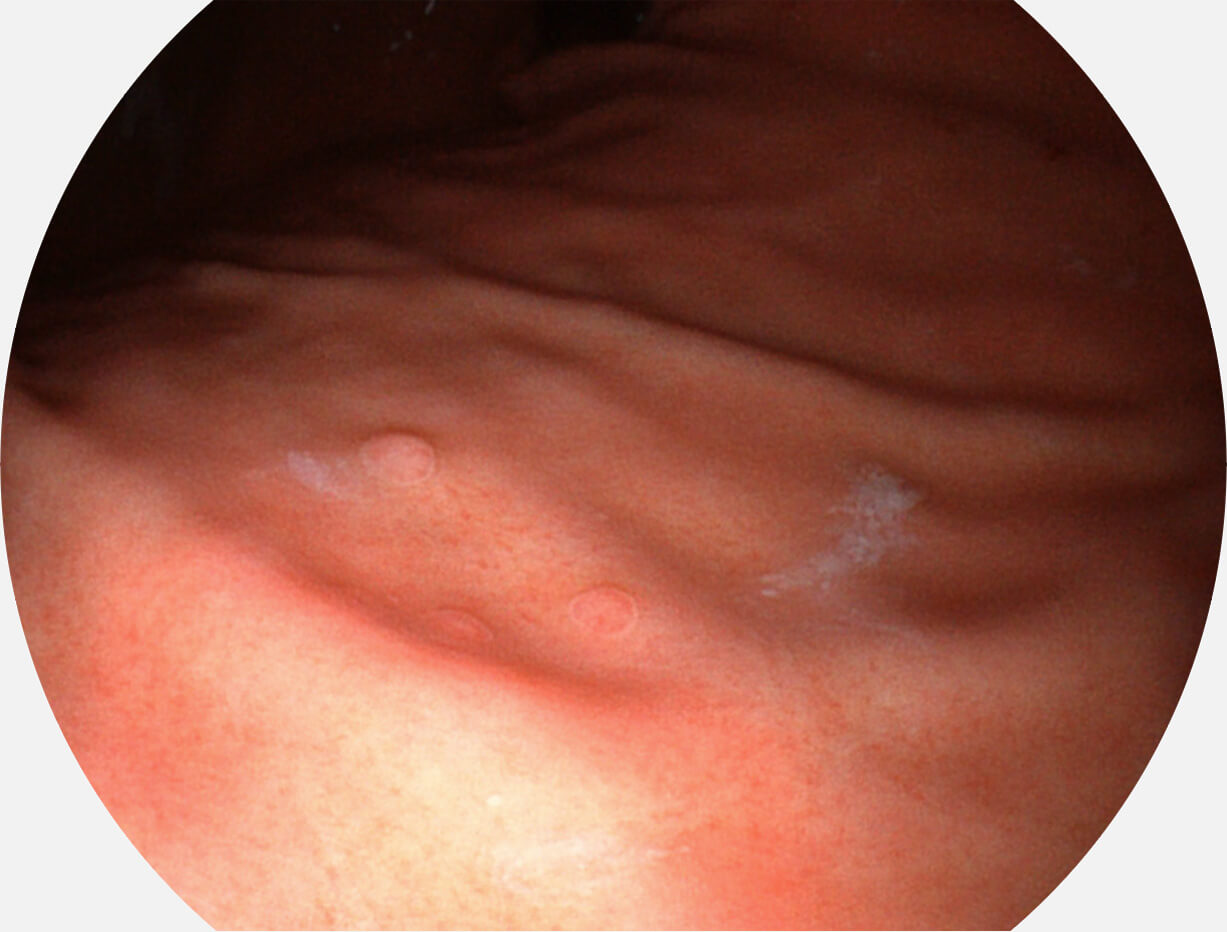

白光图像